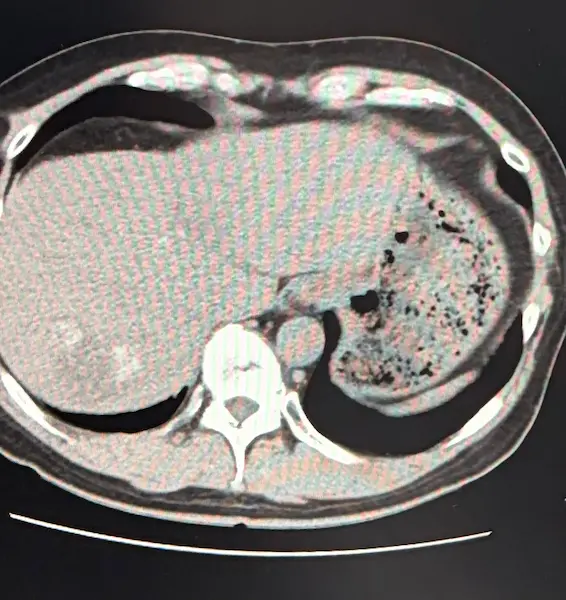

医師からそう告げられ、肝臓全体に転移したがんのCT画像を見せられた日のことは、今も忘れられません。

CT画像で肝臓全体にがんが広がっていることを自分の目でも確認。

CT検査の結果は良好でした。 肝臓に転移したがんが、目に見えて小さくなっていたのです。

肝臓に転移したがんがさらに小さくなっていました。それを証明するかのように腫瘍マーカーも下がっていました。

またCT画像では、がんが白く石灰化しているのが確認できました。腫瘍マーカーは7。ついにひと桁まで下がりました。